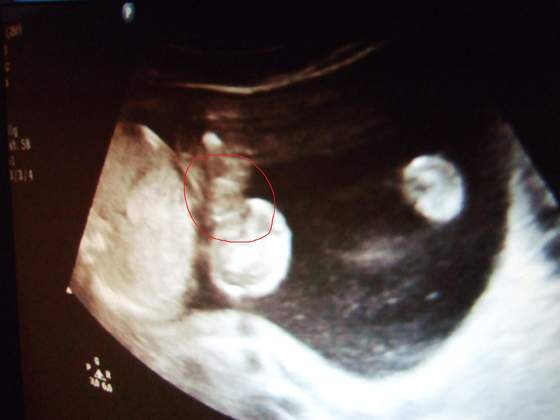

Pamiętam, jak ginekolog mówił że na USG narządy płciowe zewnętrzne chłopca wyglądają jak ślimak, zobacz dokładnie jak na Twoim zdjęciu.

moj gin mowi ze to chlopczyk - ale na tym zdj to na chlopczyka mi nie wyglada

na filmiku widac cos miedzy nozkami,ale jakos tak dziwnie nie wychodzi z jajeczek tylko od nozki z boku - dlatego tez poki co mam nadzieje na dziewczynke

gosiaczek to jest ewidentny siusiaczek

Mi lekarz w obecnej ciąży w 12 tygodniu powiedział,że będzie dziewczynka,bo... wg wiedzy czysto teoretycznej jeżeli to co jest między nóżkami odstaje do góry to będzie chłopiec jeżeli na dół to dziewczynka.U nas bardzo dobrze było widać,że odstaje w dół i będzie dziewczynka na 100%.Sprawdzałam zdjęcia usg z pierwszej ciąży również to między nóżkami było w dół